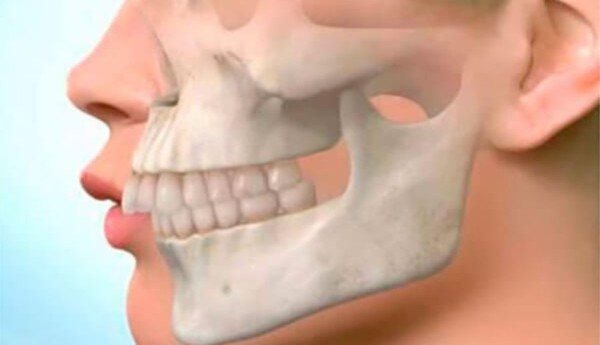

При двусторонней микрогении подбородок смещается назад, наступает обезображивание лица, известное под названием «птичье лицо». Бывает нарушение прикуса в виде глубокого резцового перекрытия.

Так называют недоразвитие нижней челюсти. Уменьшается высота нижнего отдела лица, подбородок резко скошен, что особенно заметно в профиль. Кроме выраженного эстетического недостатка почти всегда наблюдается сильная скученность зубов, изменение их правильного положения за счет меньшей длины ряда.

Лицо со скошенным и западающим назад подбородком при недоразвитии нижней челюсти называется птичьим лицом. Подобное лицо отмечается при следующих синдромах: Франческетти, Хангарта, Ульриха-Фремерей-Доны, Марфана, аглоссии-адактилии.

Кроме того, патология деформирует естественные пропорции челюстно-лицевого аппарата. Подбородок заостряется и слегка приподнимается вверх. Врачи даже дали определение этому феномену – «птичья борода».